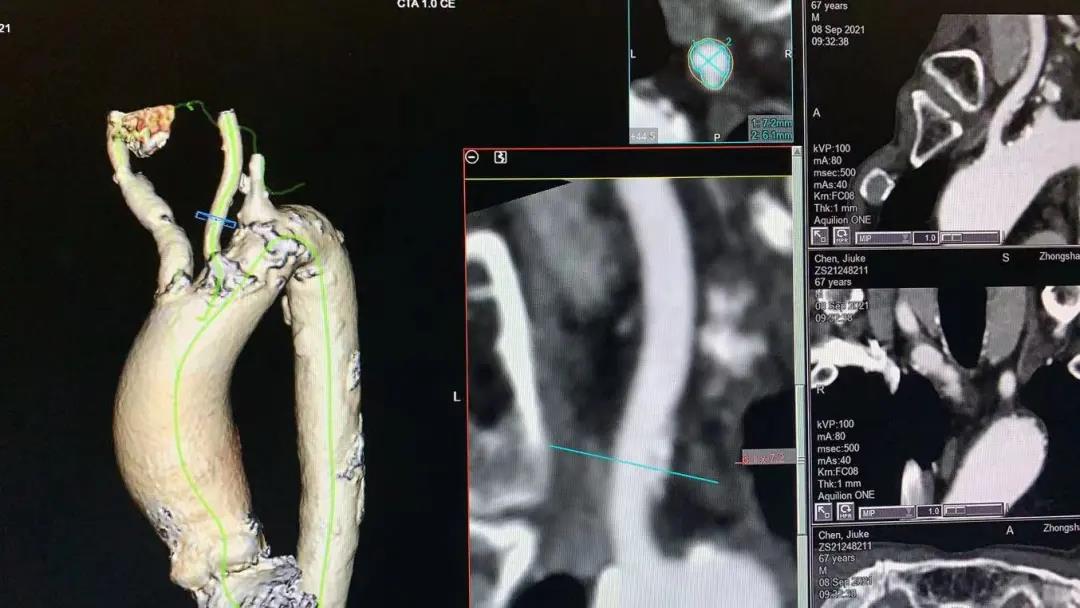

患者男性,67岁,活动后胸闷气促4年余。术前心脏超声提示先天性二叶式主动脉瓣畸形伴极重度狭窄及轻度反流,峰值流速7.1m/s,峰值压差200mmHg,平均跨瓣压差118mmHg,瓣口面积仅0.5cm2。CT评估显示主动脉瓣为Type I型二叶瓣,瓣环面积569.4mm2,测算直径26.9mm。左冠脉开口高度19.4mm,右冠脉开口高度18mm(紧邻右无冠窦交界)。该患者为重度肺气肿伴多发性肺大泡,重度肺功能不全、贫血、低血小板、虚弱,STS评分9.3%,属于外科手术高风险。

主动脉瓣瓣环 瓦式窦